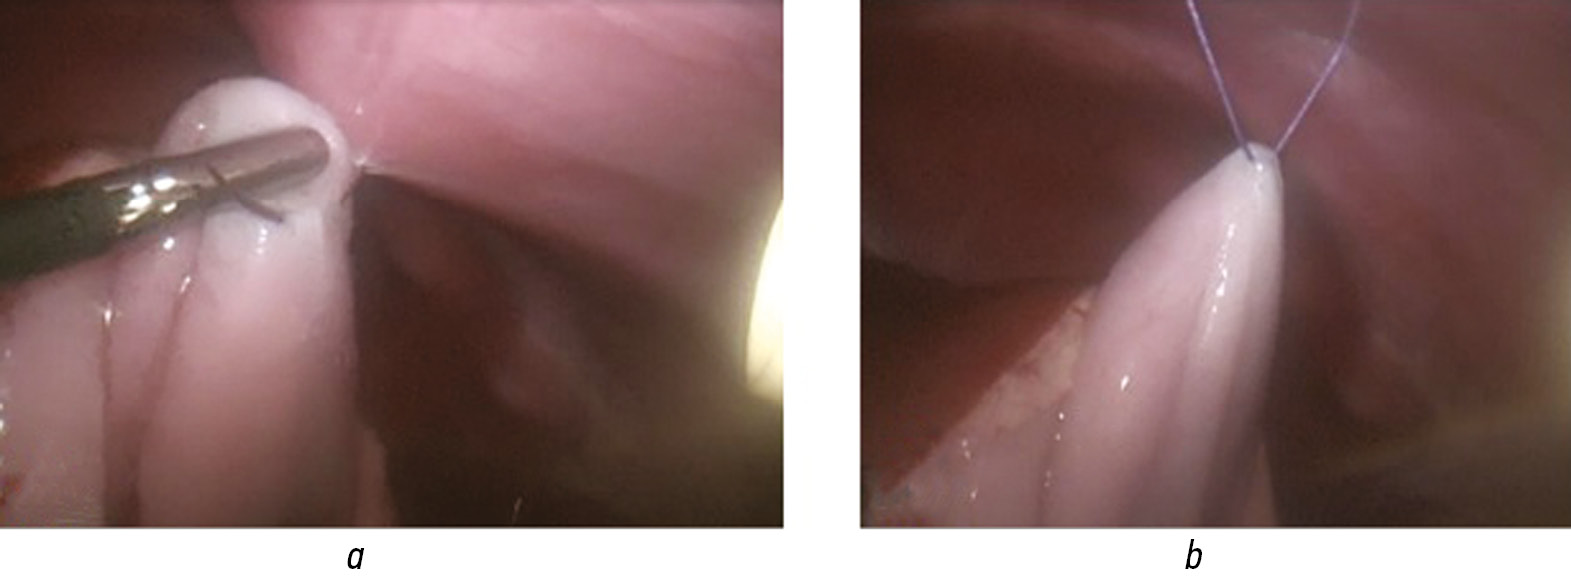

В возрасте 1 мес. 20 дней ребенку выполнена операция: лапароскопическая резекция хвоста поджелудочной железы (15 %) и резекция очага головки поджелудочной железы. Техника операции: разрез под пупком, с помощью иглы Вереша создали карбоксиперитонеум (давление 9–11 мм рт. ст, с потоком 2 л/мин), установлен 5-мм троакар с 30° оптикой. Слева и справа от пупка по срединно-ключичной линии установили 3- и 5-мм рабочие троакары. Для доступа в полость малого сальника вскрывали желудочно-ободочную связку с использованием биполярной коагуляции аппаратом Ligasure. Мобилизованный желудок по большой кривизне фиксировали к передней брюшной стенке временными тракционными швами (рис. 2).

Рис. 2. Фиксация желудка к передней брюшной стенке тракциоными швами: a — фиксация большой кривизны желудка к передней брюшной стенке; b — тракционный шов завершен

Fig. 2. Fixation of the stomach to the anterior abdominal wall with traction sutures: a — process of fixing the large curvature of the stomach to the anterior abdominal wall and b — traction seam is completed